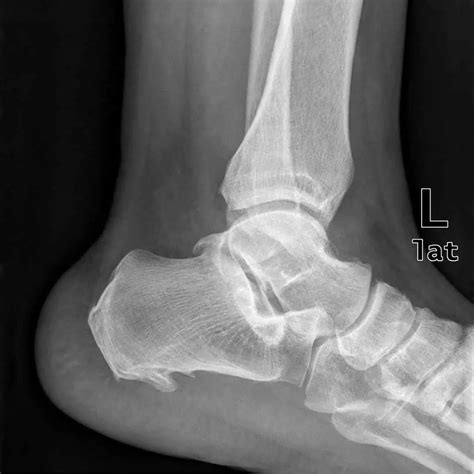

A heel spur, technically known as a calcaneal spur, is a bony protrusion that develops on the underside of the heel bone. Over time, calcium deposits build up on the heel, resulting in this outgrowth. These spurs are often associated with plantar fasciitis, a common condition that involves inflammation of the tissue running along the bottom of the foot.

It is important to note that many individuals possess heel spurs without ever experiencing any pain. The pain often stems not from the spur itself, but from the associated inflammation of the soft tissues surrounding the heel bone. This is precisely why a Heel Spur X Ray is ordered—to visualize the bone structure and help the physician determine whether the spur is the primary culprit or if other factors are contributing to your symptoms.

• Visualization: It provides a clear, high-contrast view of the heel bone, allowing the doctor to see the exact size and location of any bony growth.

Once the radiologist examines your Heel Spur X Ray, they will generate a report for your doctor. It is common for the report to confirm the presence of a "calcaneal spur." However, as mentioned previously, this does not automatically mean the spur is causing your pain. Your physician will correlate these findings with your physical symptoms. For instance, if your pain is worst in the morning or after long periods of sitting, the clinical focus will likely remain on treating the underlying plantar fasciitis, even if a spur is visible.